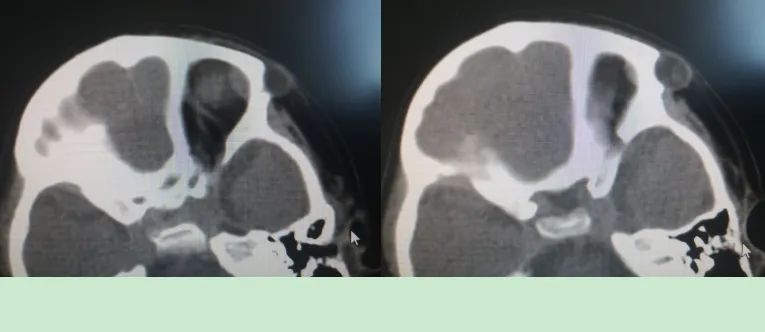

患儿经检查诊断为“左眼眶外侧肿物,性质待查”。眼部CT显示肿物已压迫颅骨,导致颅骨内凹变形,如不及时手术,可能会伤及脑组织。由于CT不能很好反映肿物侵及骨壁情况,同时患儿无法进行核磁扫描,导致肿物的性质及范围不能明确,加之眼球及眼眶内部结构复杂,这都无疑增加了手术的难度和风险。眼科全体医护人员迎难而上,不辜负救死扶伤的神圣使命,经与患儿父母进行多次交流沟通后签署了手术同意书,决定行肿物切除术,手术在全身麻醉下进行,由刘志英主任主刀,卞茹副主任医师、杨月琳医师共同协作完成。由于肿物较大,为术后恢复不影响美观,切口要尽可能小,所以手术全程精细操作,如同在葡萄皮上雕花,经过一个半小时的努力,成功将肿物完整切除,病理结果显示为良性肿瘤。患儿病情恢复良好,顺利出院。该手术的成功也推动我院眼科在眼眶病领域的诊断和治疗更向前迈进。

术前眼部CT检查

术后眼部CT检查